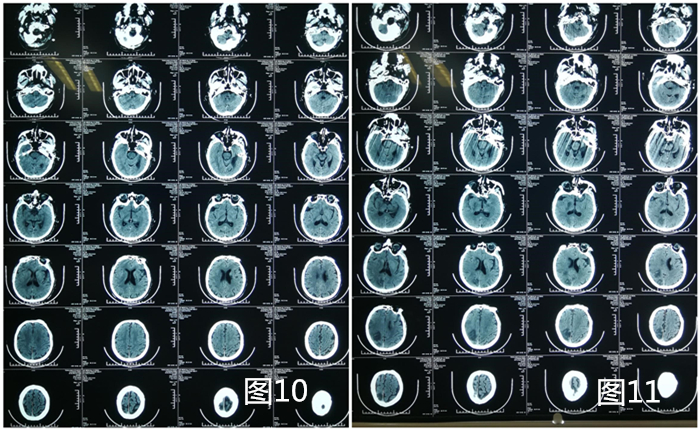

患者李XX,男性,73岁,主因“突发左侧肢体无力1小时”入院,既往房颤病史。查体:嗜睡,失语,NIHSS:18分,左侧肢体肌力0级,Babinski征(+),右侧肢体活动正常。头颅CT未见出血性改变。

因患者到我院在发病时间窗内(<4.5h),与患者家属谈话征得其同意后,急诊立即给予阿替普酶(rt-PA)静脉溶栓,同时直接将患者送入导管室,桥接行全脑血管造影术(DSA),提示右侧颈总动脉末端闭塞(图1、2)。因患者半年前于我科行全脑血管造影术提示右侧颈内动脉未见异常(图3),此次突然发病,考虑心源性栓塞。此类栓子溶栓效果差,造影也提示溶栓无效果,积极给予支架取栓治疗。

目前患者神清,可正确应答,左侧肢体肌力1级,积极康复治疗中。术前CT(图10),术后第四天CT(图11)。